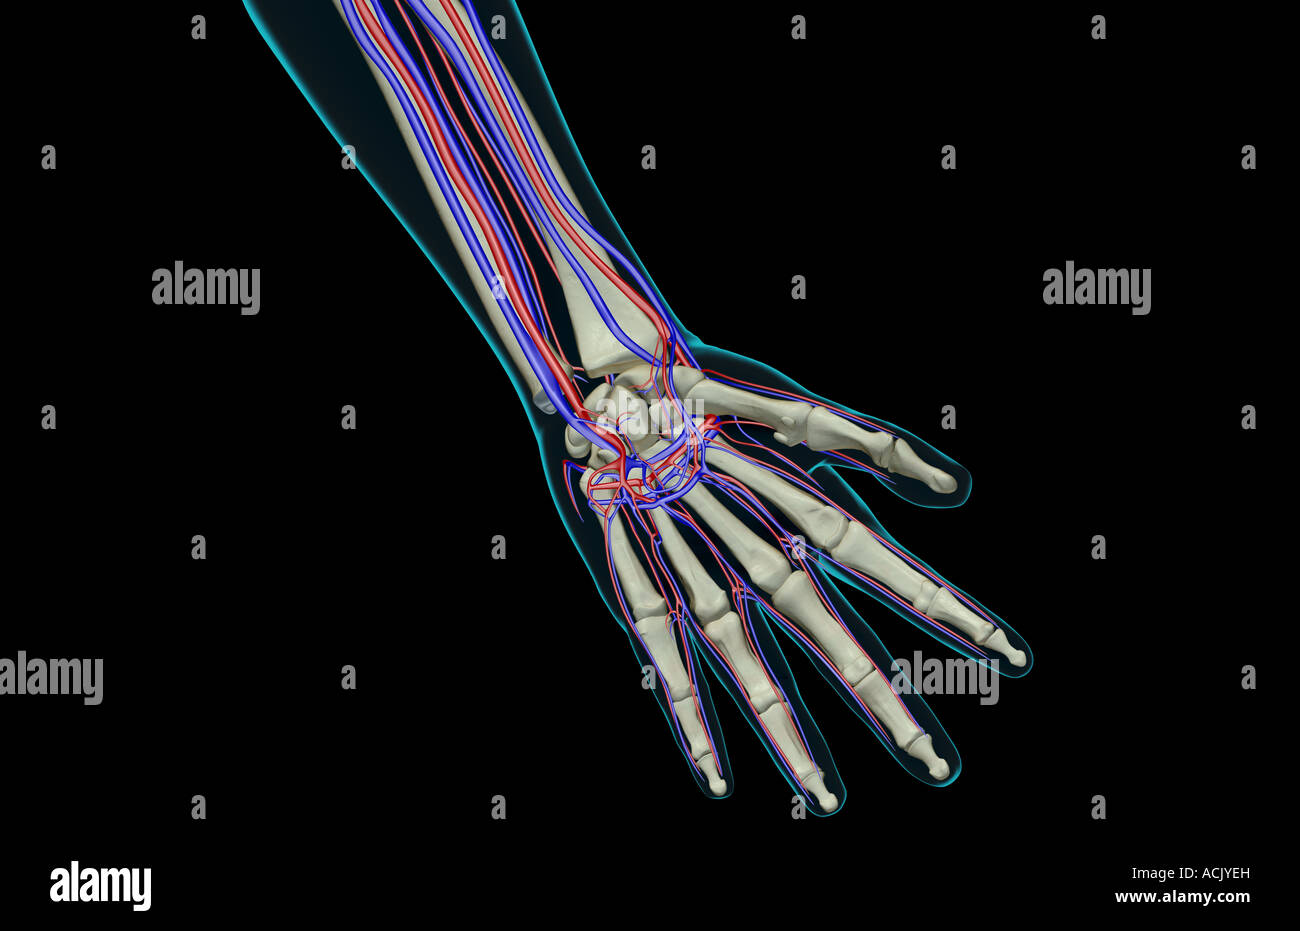

The blood supply of the hand Stock Photohttps://www.alamy.com/image-license-details/?v=1https://www.alamy.com/stock-photo-the-blood-supply-of-the-hand-13174168.html

The blood supply of the hand Stock Photohttps://www.alamy.com/image-license-details/?v=1https://www.alamy.com/stock-photo-the-blood-supply-of-the-hand-13174168.htmlRFACJYEH–The blood supply of the hand